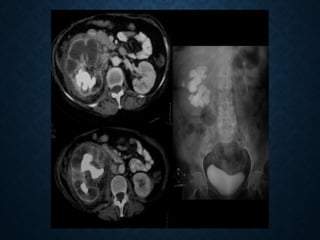

Urografía intravenosa

Ultrasonografía

TAC

 Inyección de 50cc de contraste

intravenoso

 La exploración debe incluir la

visualización de todo el sistema

colector

• Radiografías oblicuas: separa

calcificaciones superpuestas a las

siluetas renales.

• Radiografía en prono: cuando el

uréter no es completamente visible.

• Radiografía retrasada: cuando

existe retraso en el funcionamiento

de uno de los dos riñones.